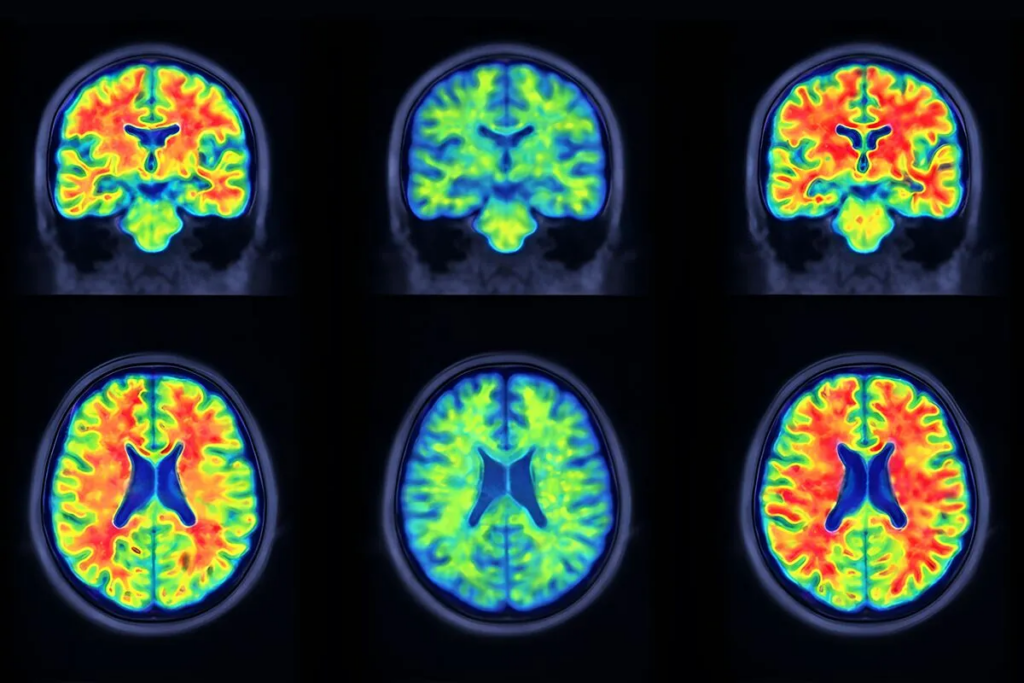

中国研究人员开发了一种名为可解释对抗分解学习(ADL)的PET分析框架,旨在将阿尔茨海默病相关的病理信号与大脑的正常背景活动区分开来。实际上,它的目标是去除视觉上的“噪声”,使临床医生能够更清晰地了解真正重要的疾病信号。

新方法采用了不同的途径。ADL 不是将扫描结果简化为一个分数,而是创建体素级病理图——可以将其视为高度精细的热图——突出显示阿尔茨海默病相关异常可能出现的位置,同时滤除可能干扰结果解读的正常生理摄取。